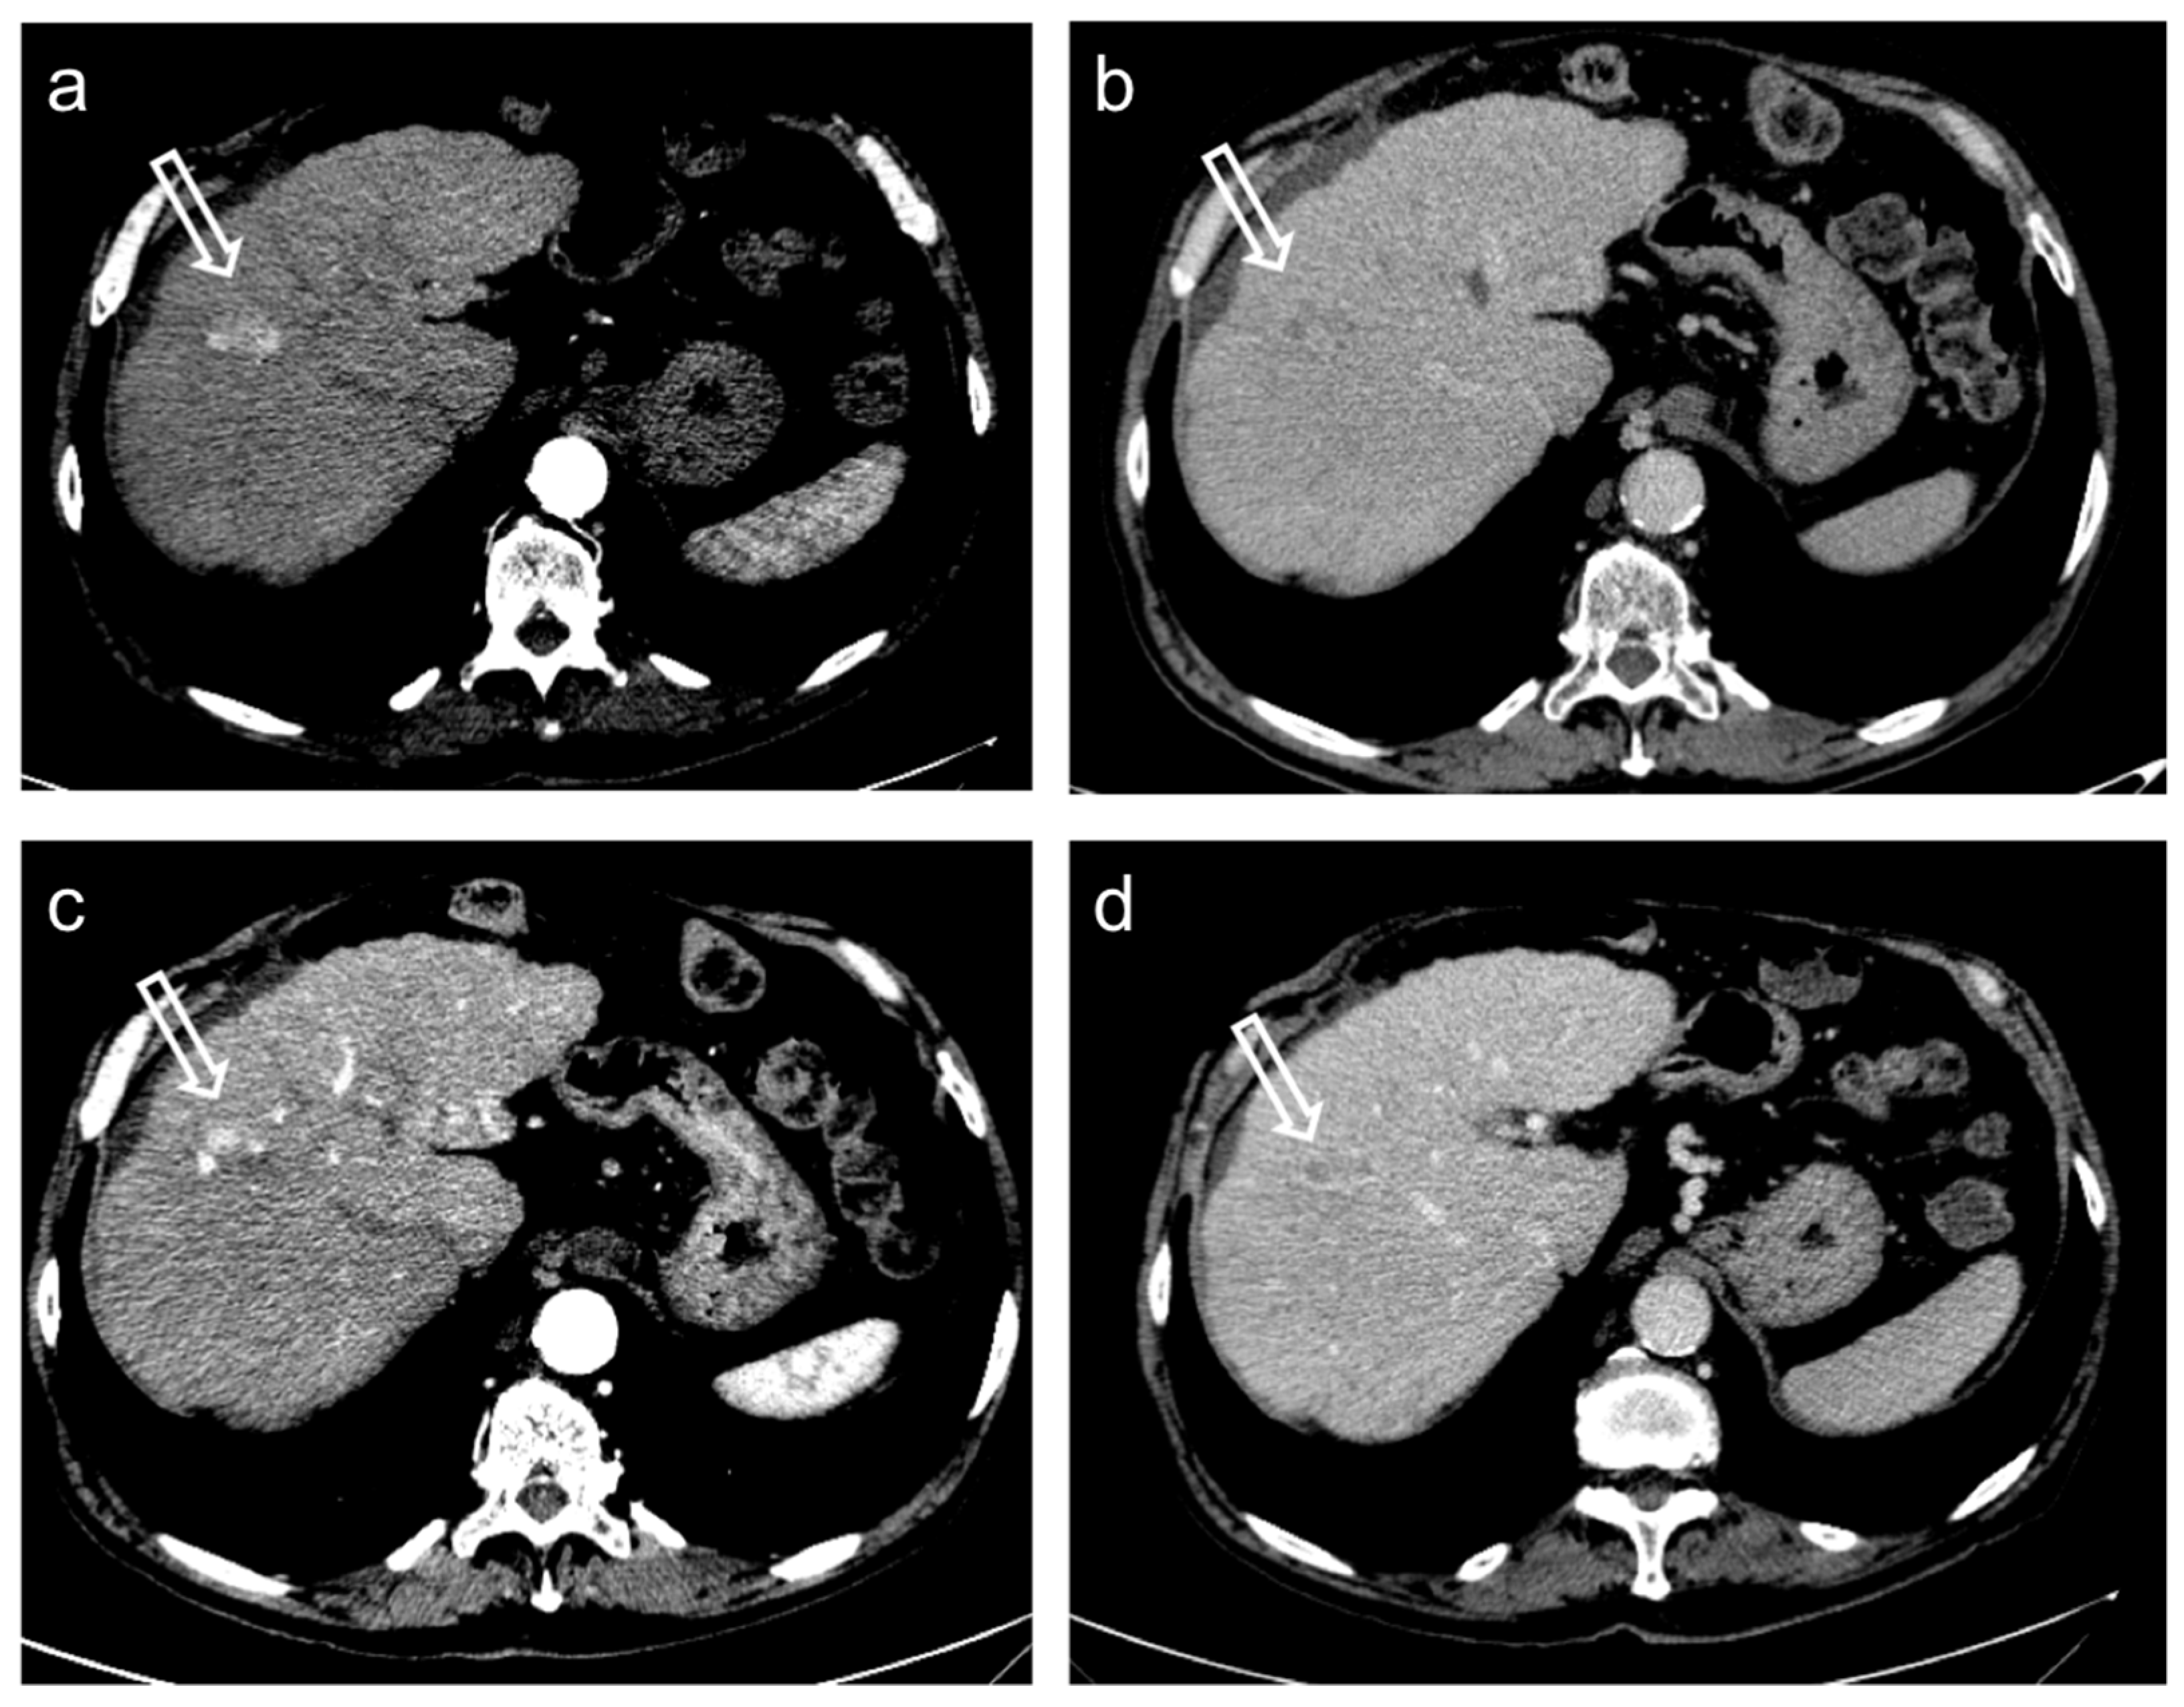

- Kielar, A.; Fowler, K.J.; Lewis, S.; Yaghmai, V.; Miller, F.H.; Yarmohammadi, H.; Kim, C.; Chernyak, V.; Yokoo, T.; Meyer, J.; et al. Locoregional therapies for hepatocellular carcinoma and the new LI-RADS treatment response algorithm. Abdom. Radiol. 2018, 43, 218–230. [Google Scholar] [CrossRef]

- Gregory, J.; Dioguardi Burgio, M.; Corrias, G.; Vilgrain, V.; Ronot, M. Evaluation of liver tumour response by imaging. JHEP Rep. 2020, 2, 100100. [Google Scholar] [CrossRef]

- Eisenhauer, E.A.; Therasse, P.; Bogaerts, J.; Schwartz, L.H.; Sargent, D.; Ford, R.; Dancey, J.; Arbuck, S.; Gwyther, S.; Mooney, M.; et al. New response evaluation criteria in solid tumours: Revised RECIST guideline (version 1.1). Eur. J. Cancer 2009, 45, 228–247. [Google Scholar] [CrossRef]

- Lencioni, R.; Llovet, J.M. Modified RECIST (mRECIST) assessment for hepatocellular carcinoma. Semin. Liver Dis. 2010, 30, 52–60. [Google Scholar] [CrossRef] [Green Version]